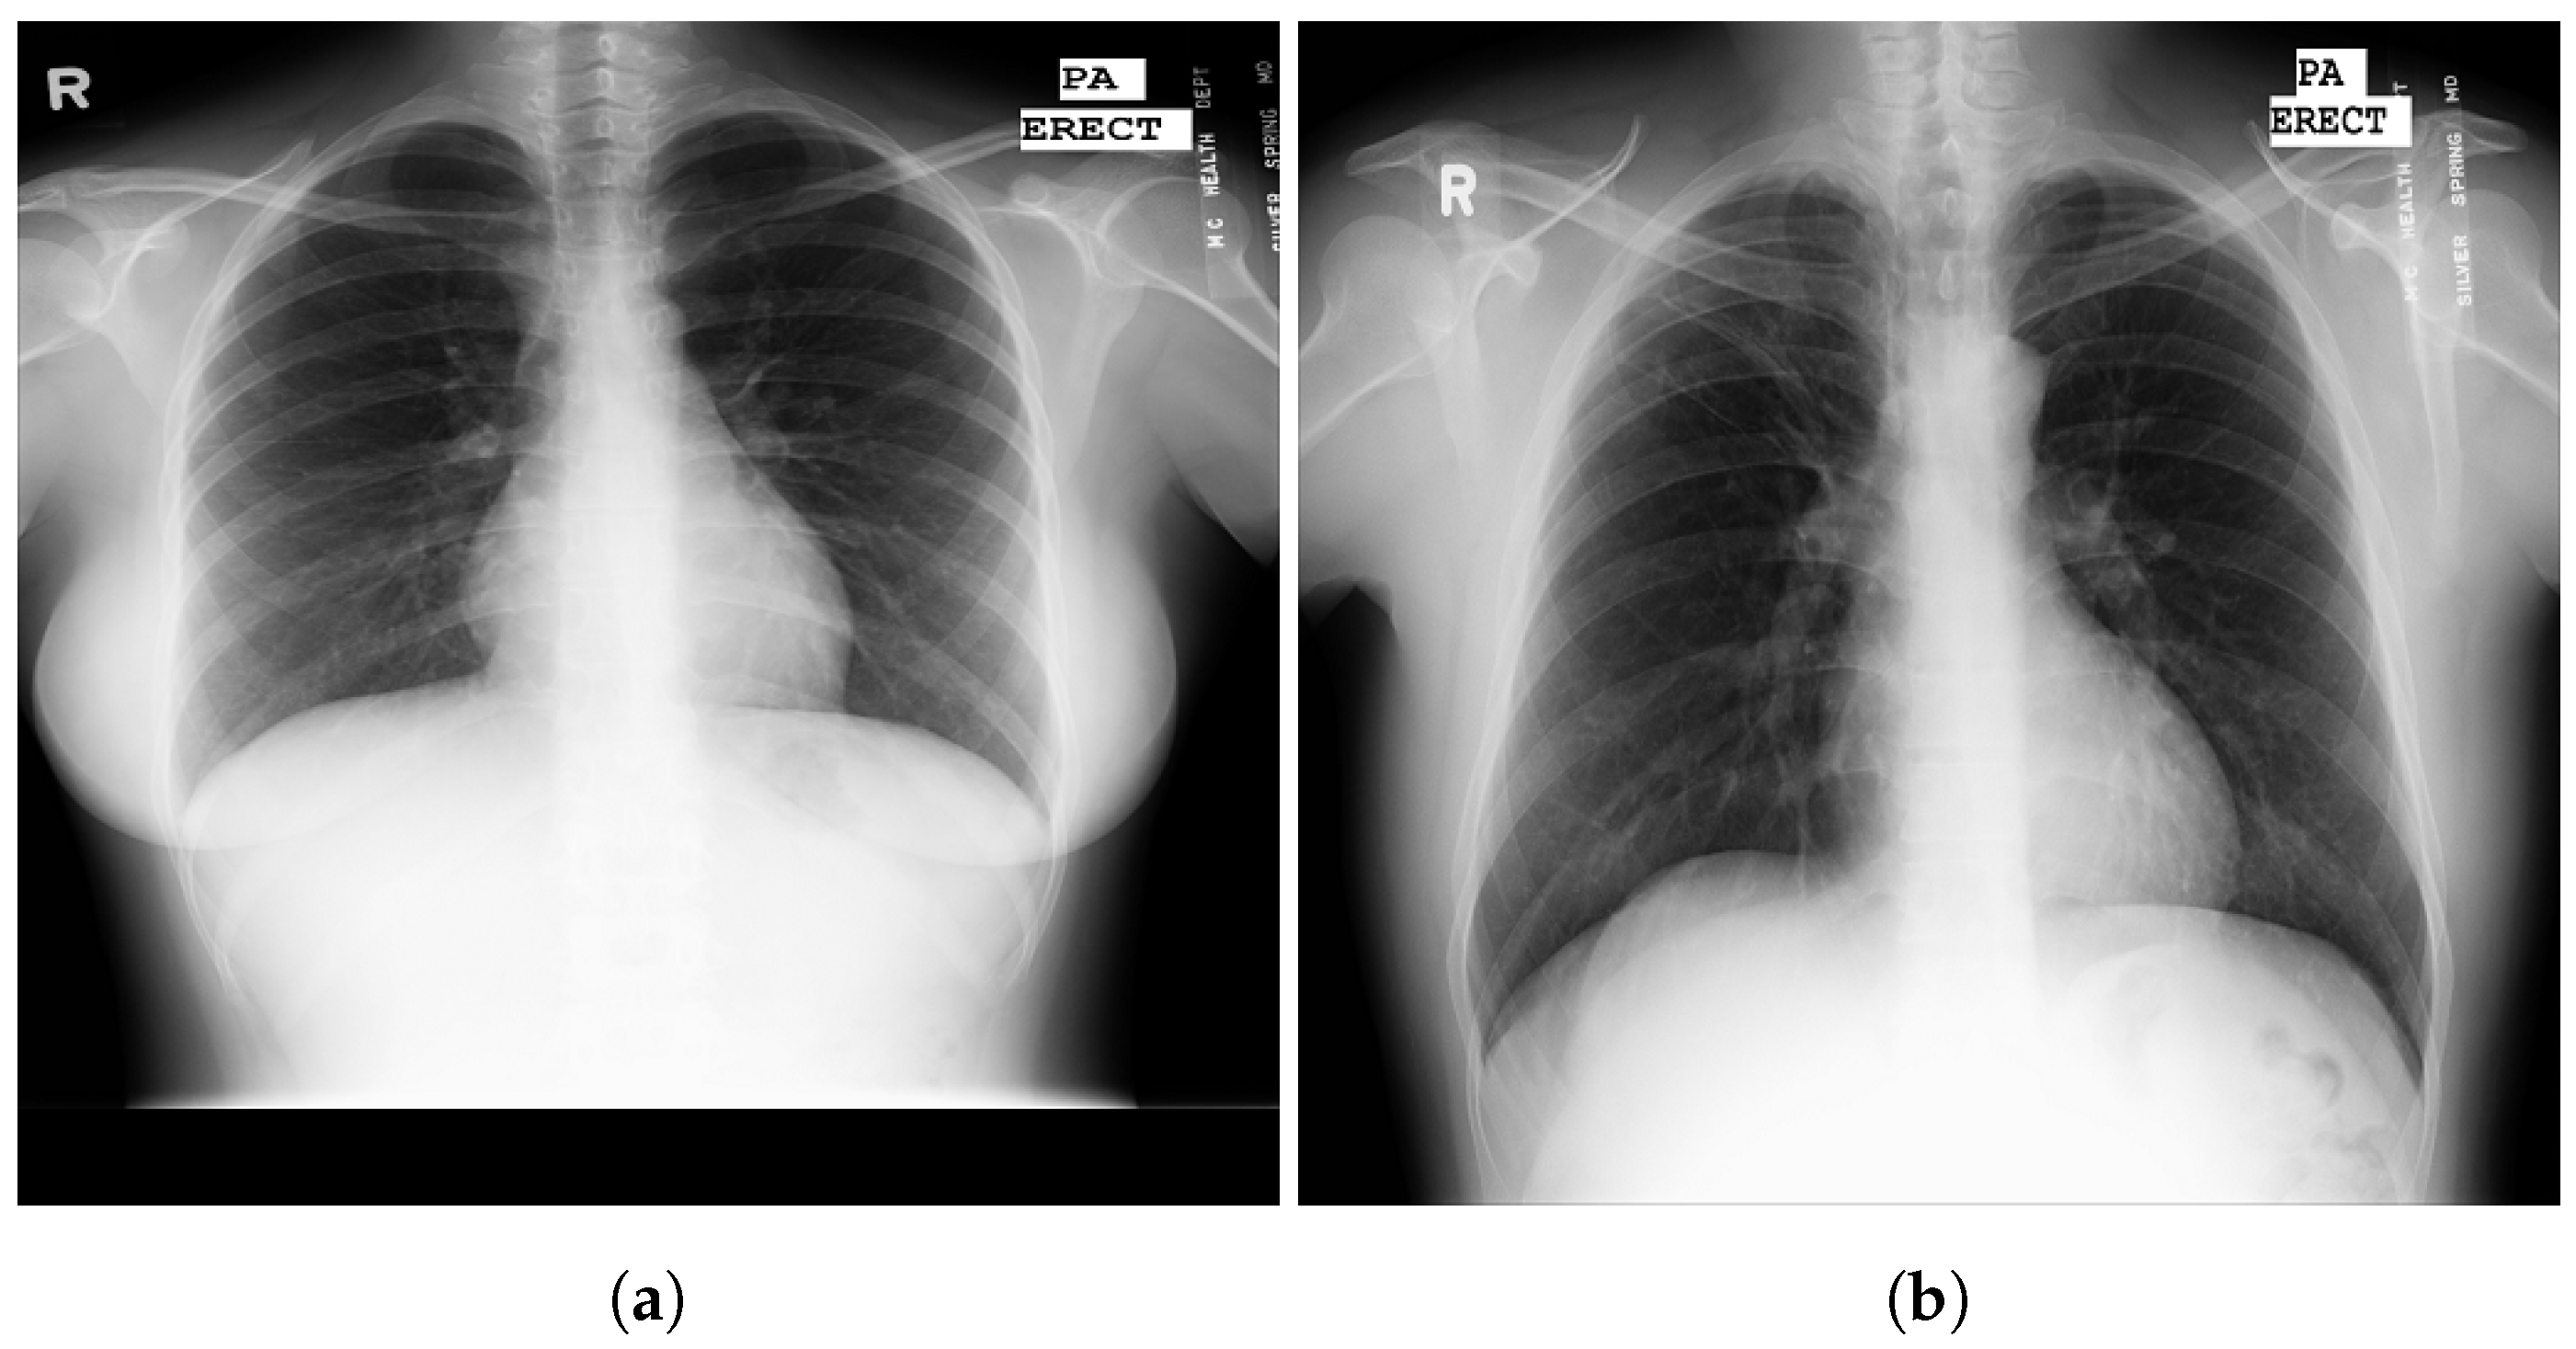

3.4. RSNA

3.5. Chest X-ray Images Pneumonia (CXRIP)